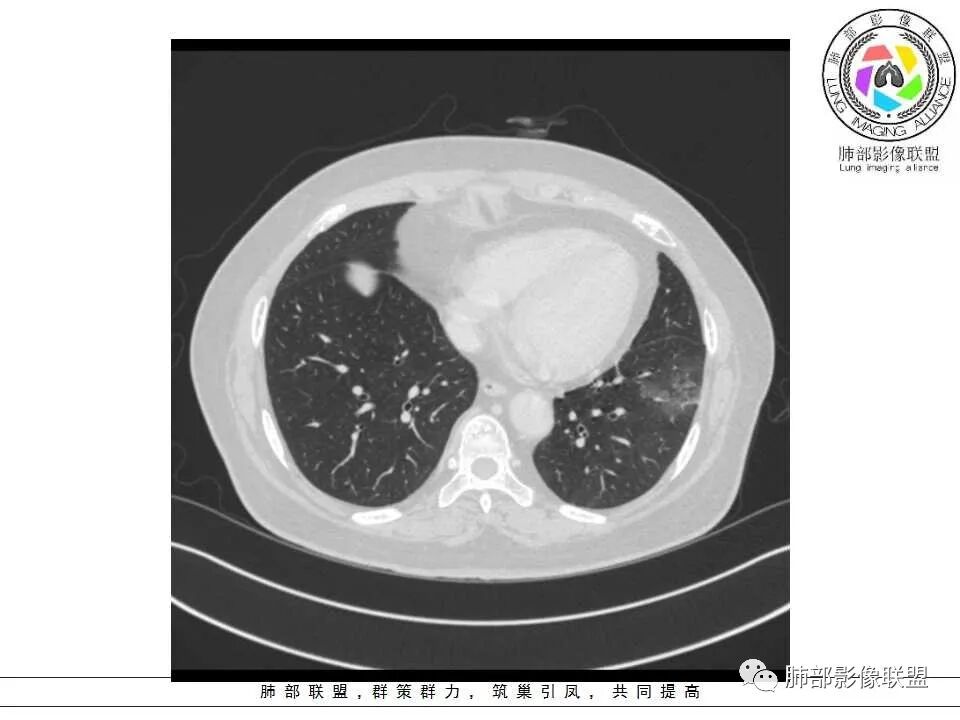

女性,65岁,左肺下叶空腔边缘见不规则结节,结节强化轻、不均匀,局部坏死边界较清楚,胸膜为糊墙为主,膈面胸膜判断不清楚似有结节;空腔内见分隔,或者数个融合,局部张力稍弱,边缘见支气管截断和血管集束;外周见大片磨玻璃影,部分边界模糊。结合病史炎症肯定有,但是囊腔结节这部分感觉恶性征象多过良性,考虑囊腔型腺癌可能性大,鉴别肺大疱感染

左肺下叶外侧基底段空洞,壁增厚,轻度强化,周围磨玻璃影,边界清晰,考虑囊腔型肺癌。

女性,65岁,咳嗽、咳痰2月余,伴发热数日。

胸CT:左肺下叶囊腔,壁厚薄不均,可见壁结节,囊腔内可见断裂小梁,部分融合,周围边界较清楚GGO,胸膜牵拉,可见血管集束、支气管充气征,冠状位部分层面可见支气管在囊腔边缘截断。考虑:囊腔型腺Ca。鉴别:肺大疱感染,CPAM等。

囊腔有张力,外形有分叶,壁厚薄不均,有间隔,有强化

1、左肺下叶外基底段不规则囊腔样病灶,囊腔内有条形影及血管穿行。

2、囊壁薄厚不均匀,稍显僵硬,有壁结节(对应边缘分叶等)、结节强化明显。

以上两条几乎将肺囊肿彻底排除在外,且高度怀疑新生物!

3、灶周环以大范围磨玻璃影,非常均匀,没有重力分布趋势,分叶状,边界隐约可变。

4、冠状位部分层面可见支气管在囊腔边缘截断。